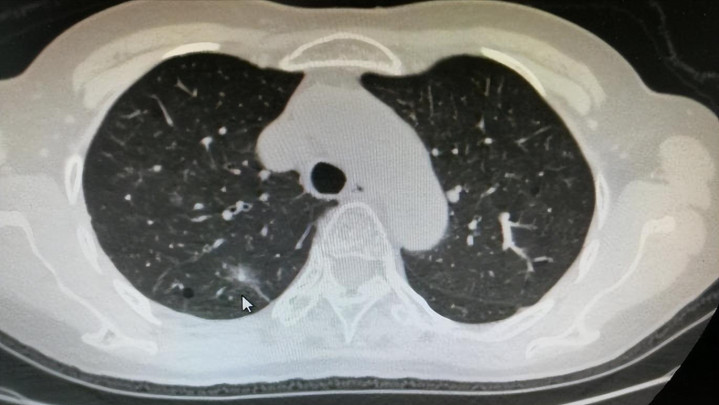

一个常年不抽烟、饮食清淡的人,在体检时被查出肺结节,他怀疑是机器出错;后来又发现,自家老人、邻居的孩子,甚至办公室里几个看起来健康的同事,也陆续有了同样的结果。

他开始问:“到底怎么回事?不抽烟也会肺结节?”更让人吃惊的是,医生告诉他,有些日常食物,比香烟更容易“点燃”肺里的小火苗。

很多人以为肺结节只是个“小阴影”,忍一忍、看着它不变大就行。但医学上早已明确,不是所有结节都无害。一些微小病变在几年内就可能演变为更严重的问题,而你每天吃下去的食物,有可能正是“助火为虐”的推手。饮食的破坏力,远超你想象。

有研究显示,我国约有超过3.5亿人存在不同形式的肺结节,其中30岁以下的年轻人占比逐年上升。